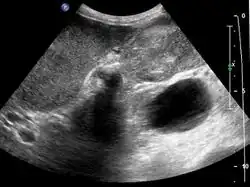

Early diagnosis is not generally possible. People at high risk, such as women or Native Americans with gallstones, are evaluated closely. Transabdominal ultrasound, CT scan, endoscopic ultrasound, MRI, and MR cholangio-pancreatography (MRCP) can be used for diagnosis. A large number of gallbladder cancers are found incidentally in patients being evaluated for cholelithiasis, or gallstone formation, which is far more common.[13] A biopsy is the only certain way to tell whether or not the tumorous growth is malignant.[14]

- Gallbladder carcinoma on ultrasound